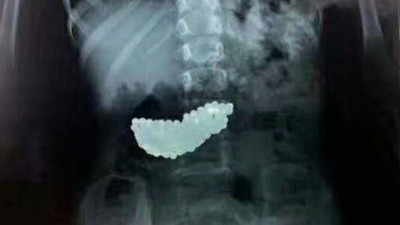

Anne-babalar dikkat! Sizin de başınıza gelebilir! 5 yaşındaki kızın mide filmi şok etti Çinli bir çocuğun midesinden, 190 adet mıknatıslı bilye çıkartıldı. 5 yaşındaki çocuğun, oyun oynarken bilyeleri yuttuğu ve 2 ay boyunca midesinde bu bilyelerle yaşadığı ortaya çıktı.